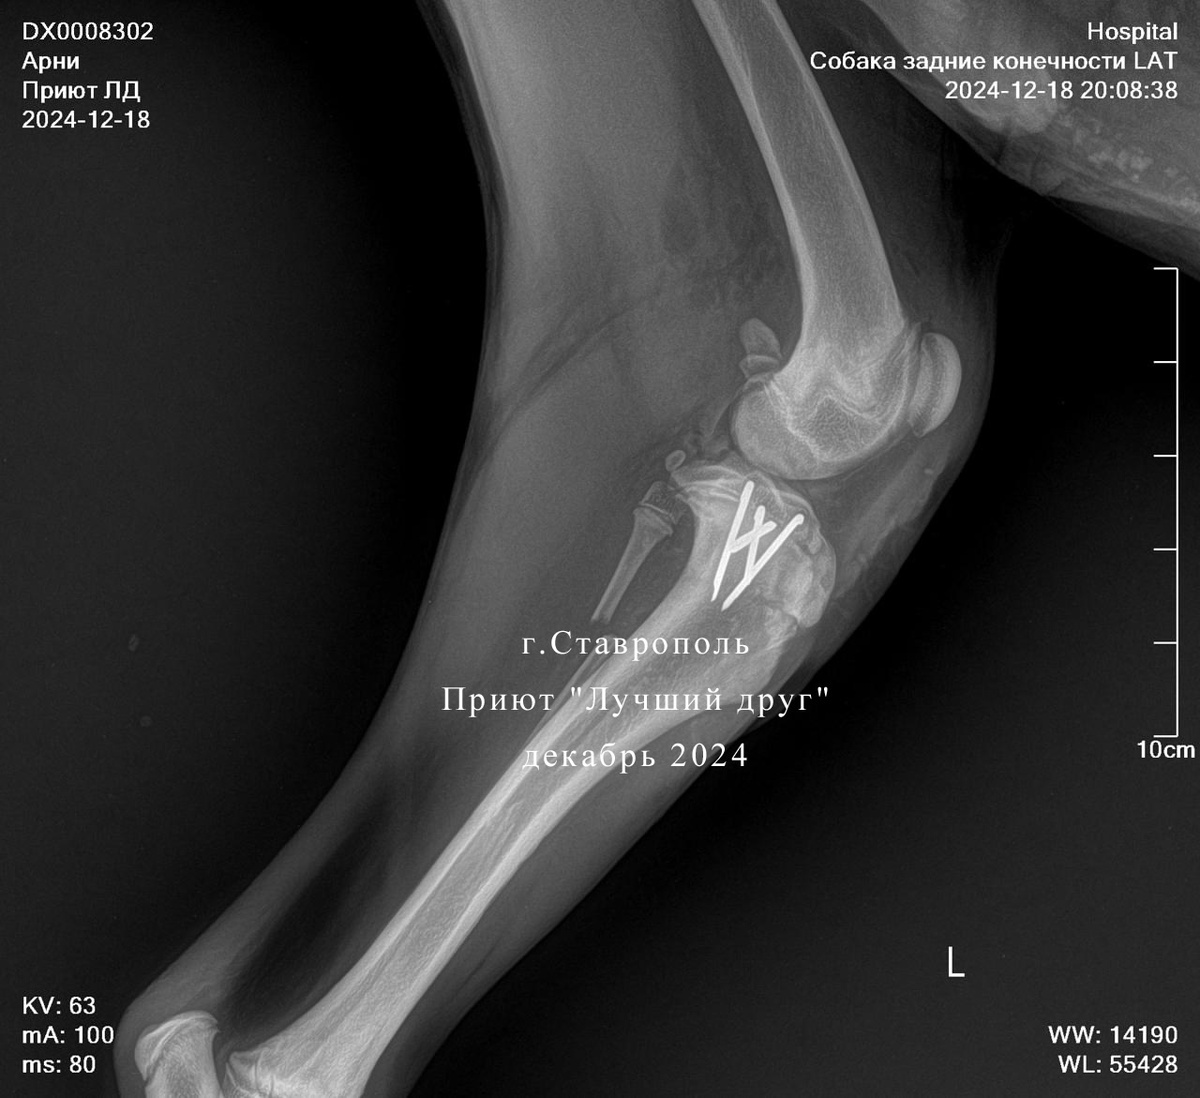

В клинике круглосуточного стационара нет, поэтому Арни, так назвали пострадавшего, отвезла девушка в Ветцентр на Серова. Состояние у пса тяжелое, разрыв селезенки и перелом передней лапы. Арни сразу забрали в операционную, с внутренними повреждениями шутить опасно. Пса после полостной операции лечили в клинике и, как только позволило его состояние,

оперировали лапы в два этапа. Сейчас Арни в приюте, чувствует себя не плохо, но, конечно же, после таких тяжелых травм восстановление не будет быстрым.